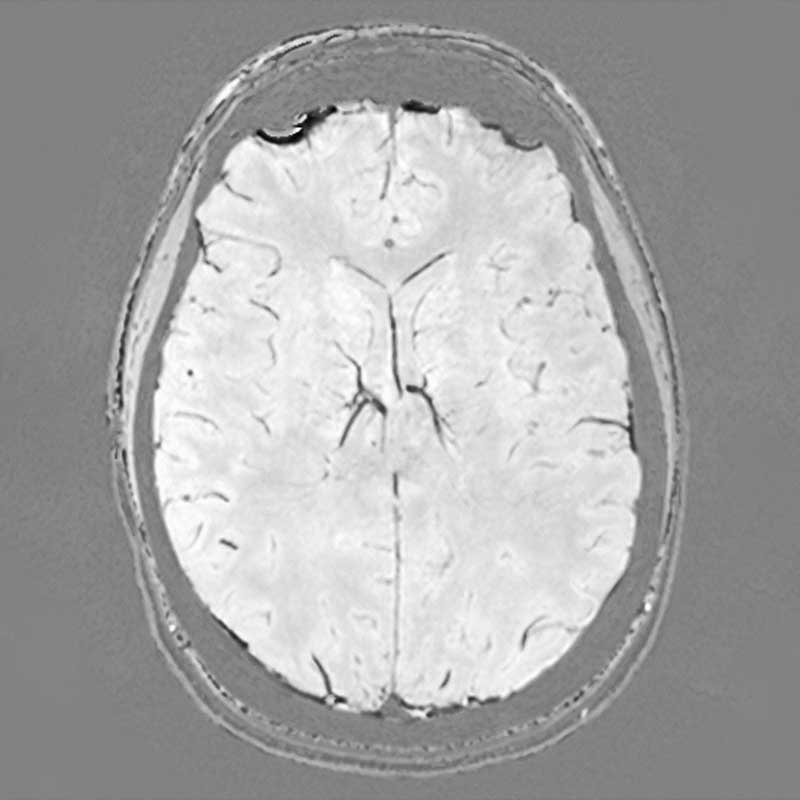

Neuroradiologie

. Ein MRT-Scan eines menschlichen Gehirns, axialer Schnitt, zeigt Strukturen und Gewebe.

T2-gewichtete HR Sequenz des Neurokraniums

. Dies ist ein MRT-Bild eines menschlichen Gehirns in horizontaler Ansicht.

Protonen-gewichtete Sequenz des Neurokraniums

. Das Bild zeigt einen MRT-Scan des menschlichen Gehirns in axialer Ansicht.

Suszeptibilitäts-gewichtete 3D-Sequenz des Neurokraniums

. Ein MRT-Scan des Gehirns mit klaren Strukturen und Details der Hirnrinde.

Coronare Double Inversion Recovery Sequenz des Neurokraniums

Um Erkrankungen des Gehirns und der Wirbelsäule zu diagnostizieren, sind modernste Technik (MRT, CT) und ein hohes Maß an Spezialisierung erforderlich. Unsere Neuroradiologie setzt modernste Großgeräte für die Bildgebung des Zentralnervensystems (ZNS). Software- und Hardwareentwicklungen erlauben es, Hirnstoffwechsel und Hirndurchblutung optimal darzustellen. Wir haben uns daneben auf die neuroradiologische Diagnostik degenerativer, traumatischer und entzündlicher Gehirn- und Rückenmarksfragestellungen spezialisiert. Dabei kooperieren wir mit dem Asklepios Fachklinikum Göttingen bei psychiatrisch-neurologischer MRT-Bildgebung. Diagnostik und minimalinvasiver Therapie degenerativer Wirbelsäulenerkrankungen ist Teil unseres Wirbelsäulenzentrums.